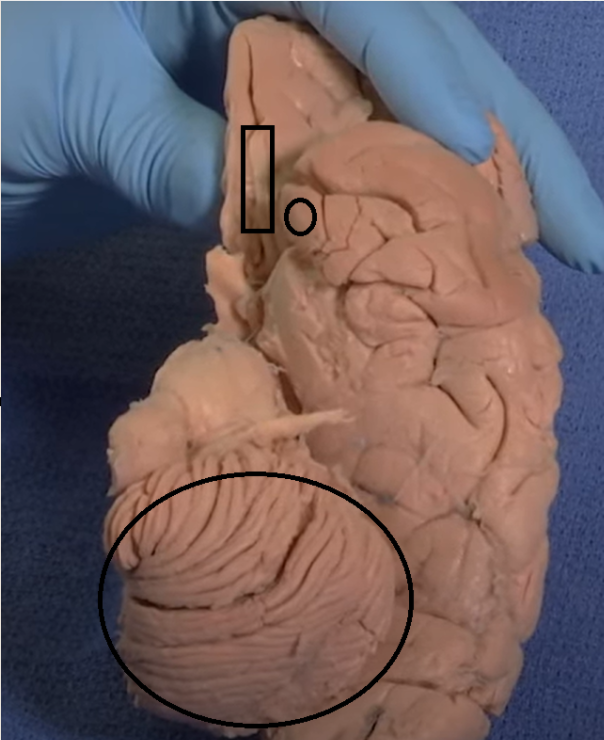

The purple hippocampus is visualized tracing the ventricular system (turquoise).